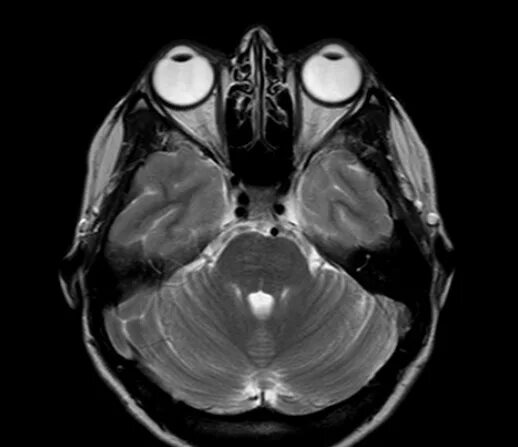

Мрт орбит и зрительных нервов